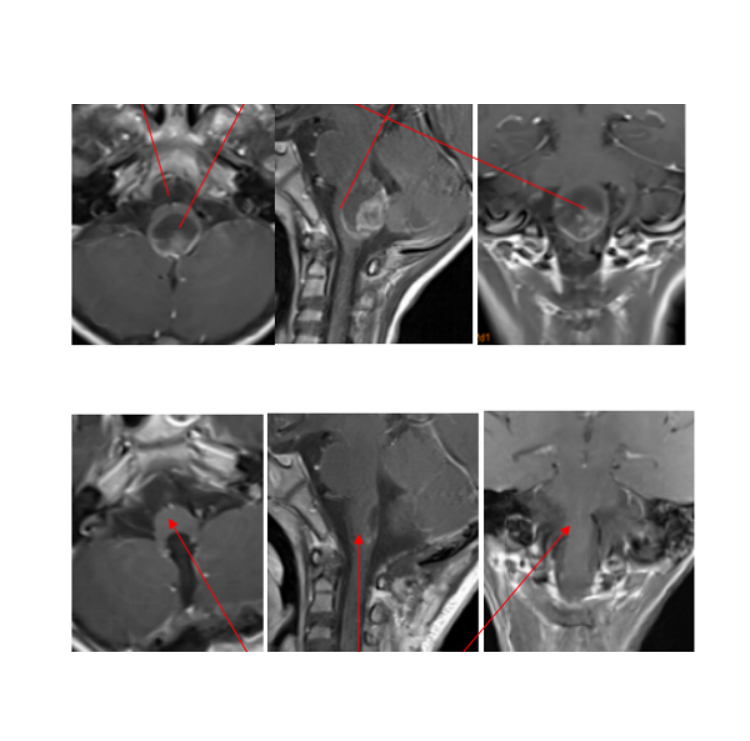

案例2:7岁,轩轩,脑干间变型室管膜瘤,在INC帮助下,在德国肿瘤全切术后,受压延髓逐渐复原。

德国手术前后影像资料对比